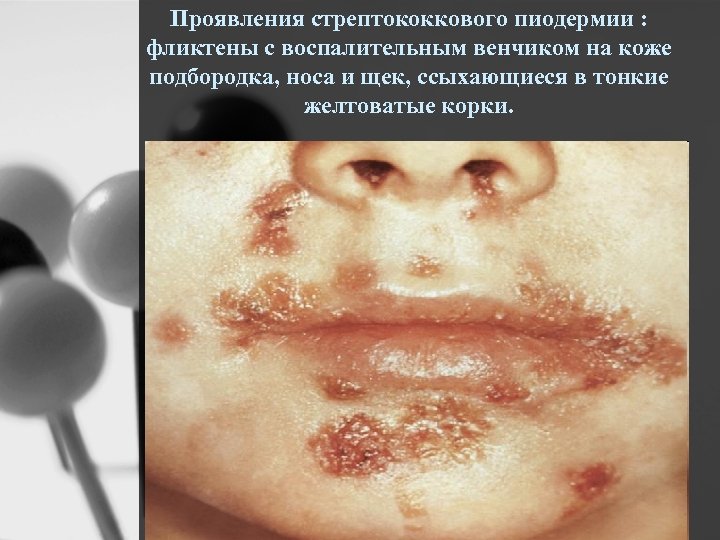

Проявления стрептококкового пиодермии : фликтены с воспалительным венчиком на коже подбородка, носа и щек, ссыхающиеся в тонкие желтоватые корки.

Проявления стрептостафилококкового пиодермии: фликтены вокруг рта и носа, ссыхающиеся в толстые желтые слоистые корки